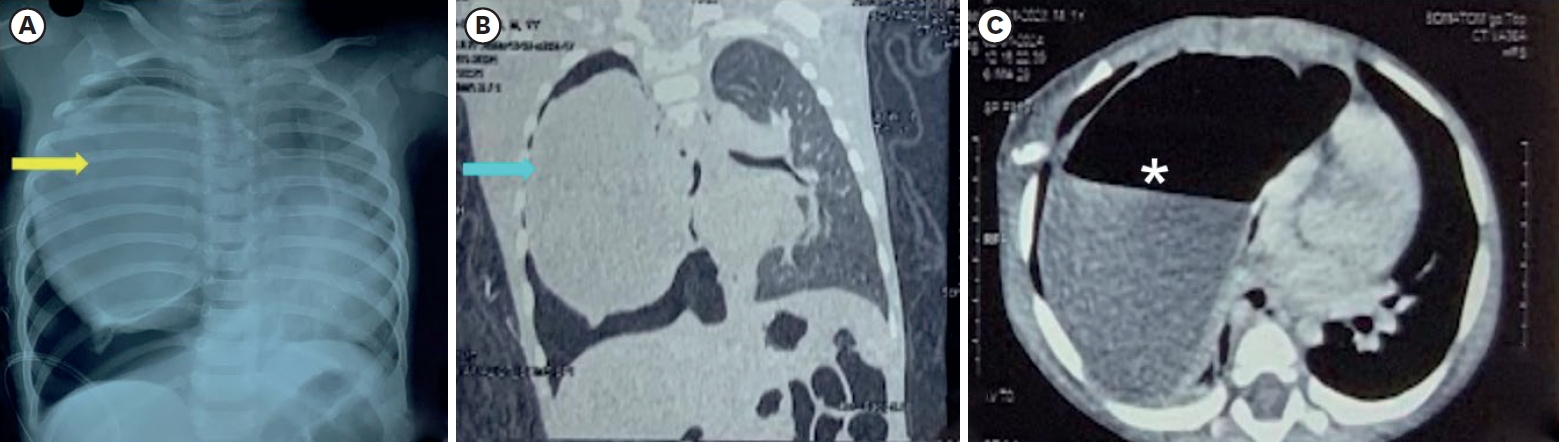

A chest radiograph showed a space-occupying lesion in the right hemithorax (Fig. 1A). High-resolution computed tomography (CT) (Fig. 1B and C) revealed a large cystic lesion measuring 8.8 cm × 8 cm × 6 cm in the right hemithorax, with air-fluid levels in the mid and lower zones, causing a mediastinal shift to the left. Additional smaller cysts were noted but no aberrant vessels were identified. A provisional diagnosis of congenital pulmonary airway malformation (CPAM) versus bronchogenic cyst was made.

Fig. 1.

Radiologic findings.

(A) Chest radiograph at the time of admission showing a cystic lesion in the right hemithorax causing mediastinal shift along with right pneumothorax probably secondary to the chest tube insertion (yellow arrow indicates the cystic lesion). (B) Coronal view of high-resolution computed tomography showing 8.8 cm × 8 cm × 6 cm smooth-walled cystic lesion occupying almost the entire right hemithorax (blue arrow indicates the cystic lesion). (C) Axial view of high-resolution computed tomography (mediastinal window) showing a cystic lesion with air-fluid level (asterisk) in the right hemithorax.